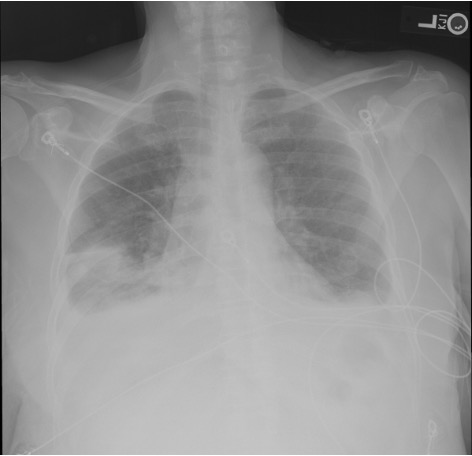

Post-procedure imaging

Post-procedure ultrasound showing reduced right pleural effusion Post-procedure CXR showing interval improvement after thoracentesis